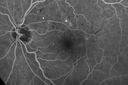

Diabetic Macular Ischemia - Enlarged FAZ - OCT-A447 views70 year old female diagnosed with diabetes 2 years ago. Her blood pressure was normal at 116/73. She has vision loss for 6 months in both eyes. VA is 20/100 OU. OCT-A shows macular ischemia.

Diabetic Macular Ischemia - Enlarged FAZ - OCT-A432 views70 year old female diagnosed with diabetes 2 years ago. Her blood pressure was normal at 116/73. She has vision loss for 6 months in both eyes. VA is 20/100 OU. OCT-A shows macular ischemia.

Diabetic Macular Ischemia - Enlarged FAZ - OCT-A426 views70 year old female diagnosed with diabetes 2 years ago. Her blood pressure was normal at 116/73. She has vision loss for 6 months in both eyes. VA is 20/100 OU. OCT-A shows macular ischemia.

Diabetic Macular Ischemia - Enlarged FAZ - OCT-A395 views70 year old female diagnosed with diabetes 2 years ago. Her blood pressure was normal at 116/73. She has vision loss for 6 months in both eyes. VA is 20/100 OU. OCT-A shows macular ischemia.